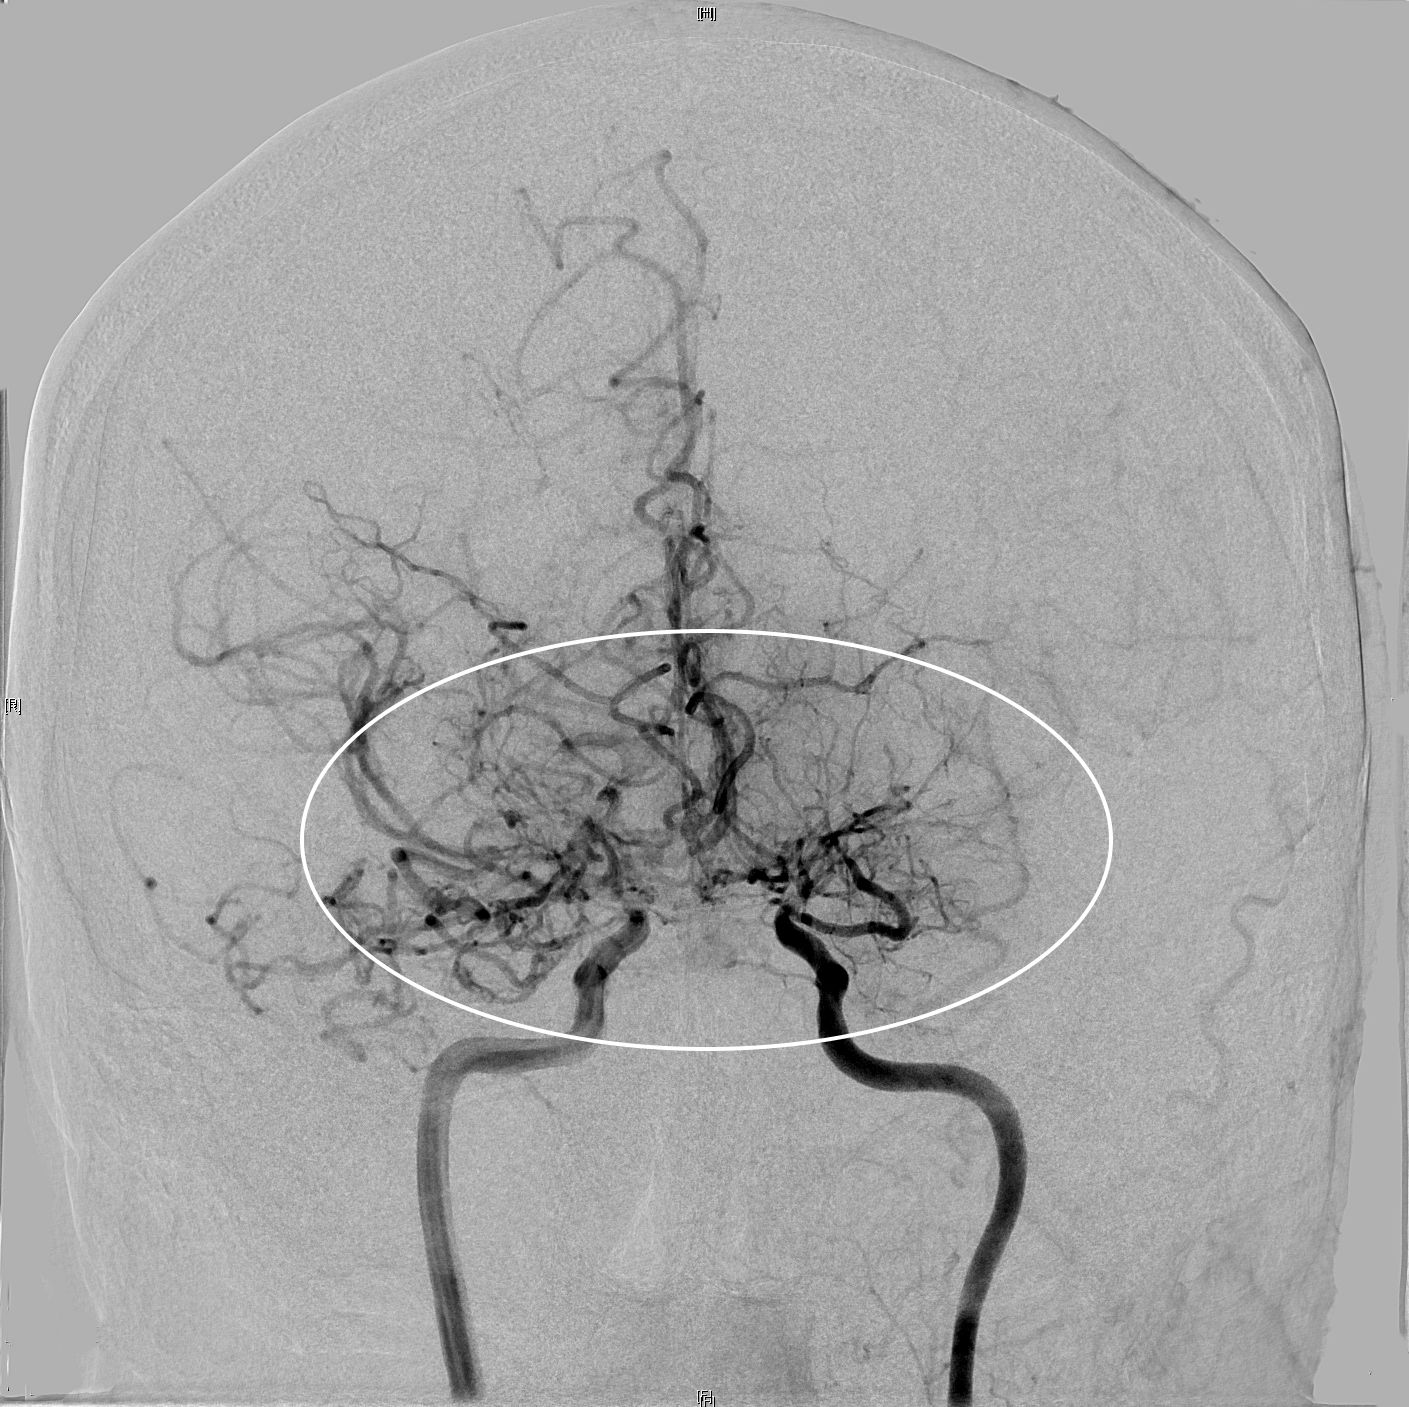

Zunächst wird bei allen Teilnehmerinnen und Teilnehmern die Duchblutung und die Krankheitsaktivität genau bestimmt. Dies geschieht mit den neuesten Methoden der Bildgebung:

MRT-basierte hochauflösende Darstellung der Gefäßwand der betroffenen Arterien

Entsprechend der Untersuchungsergebnisse erfolgen dann weitere Verlaufskontrollen oder die patientenindividuelle Therapie durch gezielte mikrochirurgisch angelegte Gefäß-Bypässe.

Wir identifizieren die Patientinnen und Patienten, die einen, mehrere oder keinen Bypass benötigen und legen diese an. So kann gewährleistet werden, dass die angelegten Bypässe funktionieren und die Patientinnen und Patienten keine weiteren Schlaganfälle erleiden.

Beste verfügbare Diagnostik

Die Patientinnen und Patienten erhalten durch die Teilnahme an der Studie die aktuell beste verfügbare bildgebende Diagnostik mit MRT und Positronen-Emissions-Tomographie (PET/CT). Insbesondere das PET/CT wird häufig von den Krankenkassen nicht gezahlt. Im Rahmen dieser Studie steht den Teilnehmerinnen und Teilnehmern das PET/CT kostenfrei zur Verfügung.